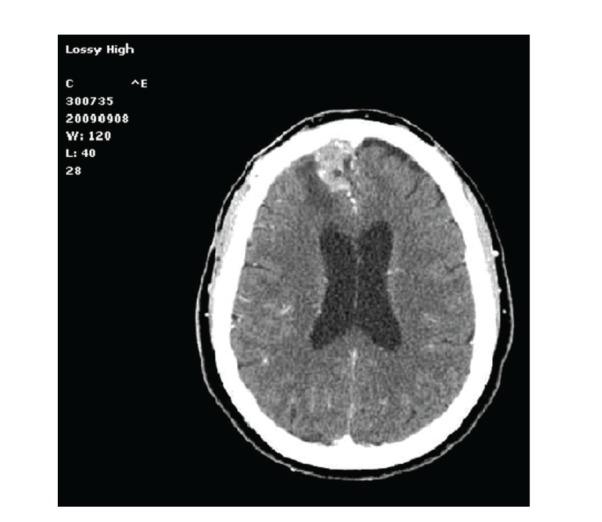

Background. Numerous reports have demonstrated how postoperative intracranial granulomas can often mimic neoplasm clinically, radiologically, and even macroscopically. Herein we present an unusual case of postsurgical intracranial aseptic granuloma secondary to a chronic inflammatory reaction without any identifiable retained foreign body. Case Description. A 71-year-old patient started complaining of severe headache seven months after surgical excision of WHO Grade I right frontal falx meningioma. CT and MRI scans disclosed a contrast-enhanced lesion with diffuse mass effect in the previous surgical site. The lesion was resected; intraoperative finding and histological specimens led to the diagnosis of postoperative granuloma, likely expression of a glial reaction to the fluid absorbable hemostatics applied in the surgical site after meningioma excision. The possible granuloma-inducing materials and the timing of granuloma formation are discussed. Conclusion. A comprehensive analysis of clinical and neuroradiological data, as well as results of blood tests including positive and negative acute phase proteins, is mandatory to raise the suspicion of postoperative granuloma. The treatment options should be evaluated on a case-by-case basis, with a conservative attitude being the one of choice only for patients without progressive neurological deficit. Alternatively, aggressive surgical treatment and histopathological examination should be advocated.

背景。大量报告表明,术后颅内肉芽肿在临床、放射学甚至宏观层面上常常可模拟肿瘤。在此,我们呈现一例不寻常的术后颅内无菌性肉芽肿病例,其继发于慢性炎症反应,且无任何可识别的残留异物。病例描述。一名71岁患者在世界卫生组织一级右额镰旁脑膜瘤手术切除七个月后开始主诉严重头痛。CT和MRI扫描显示在先前手术部位有一个强化病变,伴有弥漫性占位效应。该病变被切除;术中发现及组织学标本诊断为术后肉芽肿,可能是对脑膜瘤切除后手术部位应用的可吸收液体止血剂的胶质反应表现。讨论了可能诱发肉芽肿的物质及肉芽肿形成的时间。结论。对临床和神经放射学数据以及包括正负急性期蛋白在内的血液检查结果进行全面分析,对于提高对术后肉芽肿的怀疑至关重要。治疗方案应逐案评估,对于无进行性神经功能缺损的患者,保守态度是首选。或者,应提倡积极的手术治疗和组织病理学检查。